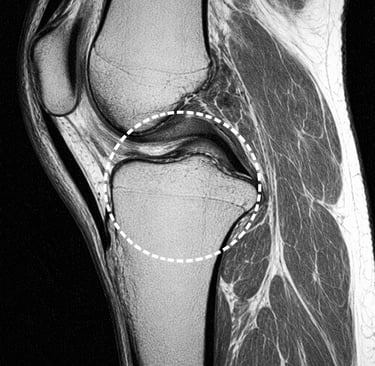

IRM du genou

Lésion du ménisque

Une lésion du ménisque peut provoquer une douleur lors de certains mouvements du genou.